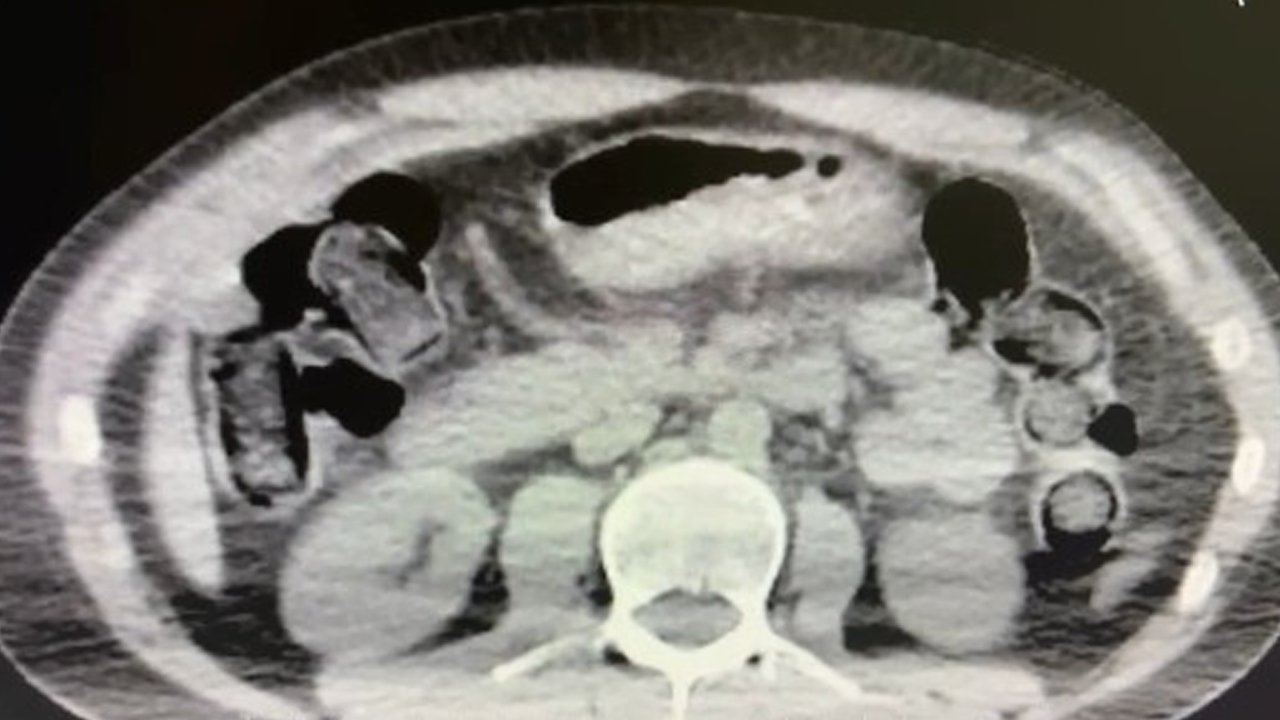

Nevşehir İl Emniyet Müdürlüğü Narkotik Suçlarla Mücadele Şube Müdürlüğü ekipleri, kentte uyuşturucu ve uyarıcı madde ticareti yapmak ve kullanmak suretiyle vatandaşları zehirleyen sokak satıcılarına yönelik çalışma başlattı. Cumhuriyet Başsavcılığı koordinesinde çalışmalarını yoğunlaştıran ekipler, şüpheliler S.B. ve O.R.'nin 'yutma yöntemi' ile kente uyuşturucu madde sevk edeceği bilgisi üzerine operasyon düzenledi.

Şüphelilerin ikametlerinde ve araçlarında yapılan aramada 101 kapsül halinde 722 gram uyuşturucu madde, 1 adet hassas terazi, uyuşturucu madde sevkiyatında yutma yönteminde kullanılan muhtelif materyaller, uyuşturucu madde ticaretinden elde edilen 20 bin 210 TL, bin 320 euro ve 10 ABD doları ele geçirildi. Emniyetteki işlemlerinin ardından adliyeye sevk edilen 2 şüpheli, çıkarıldıkları mahkemece tutuklanarak cezaevine gönderildi.